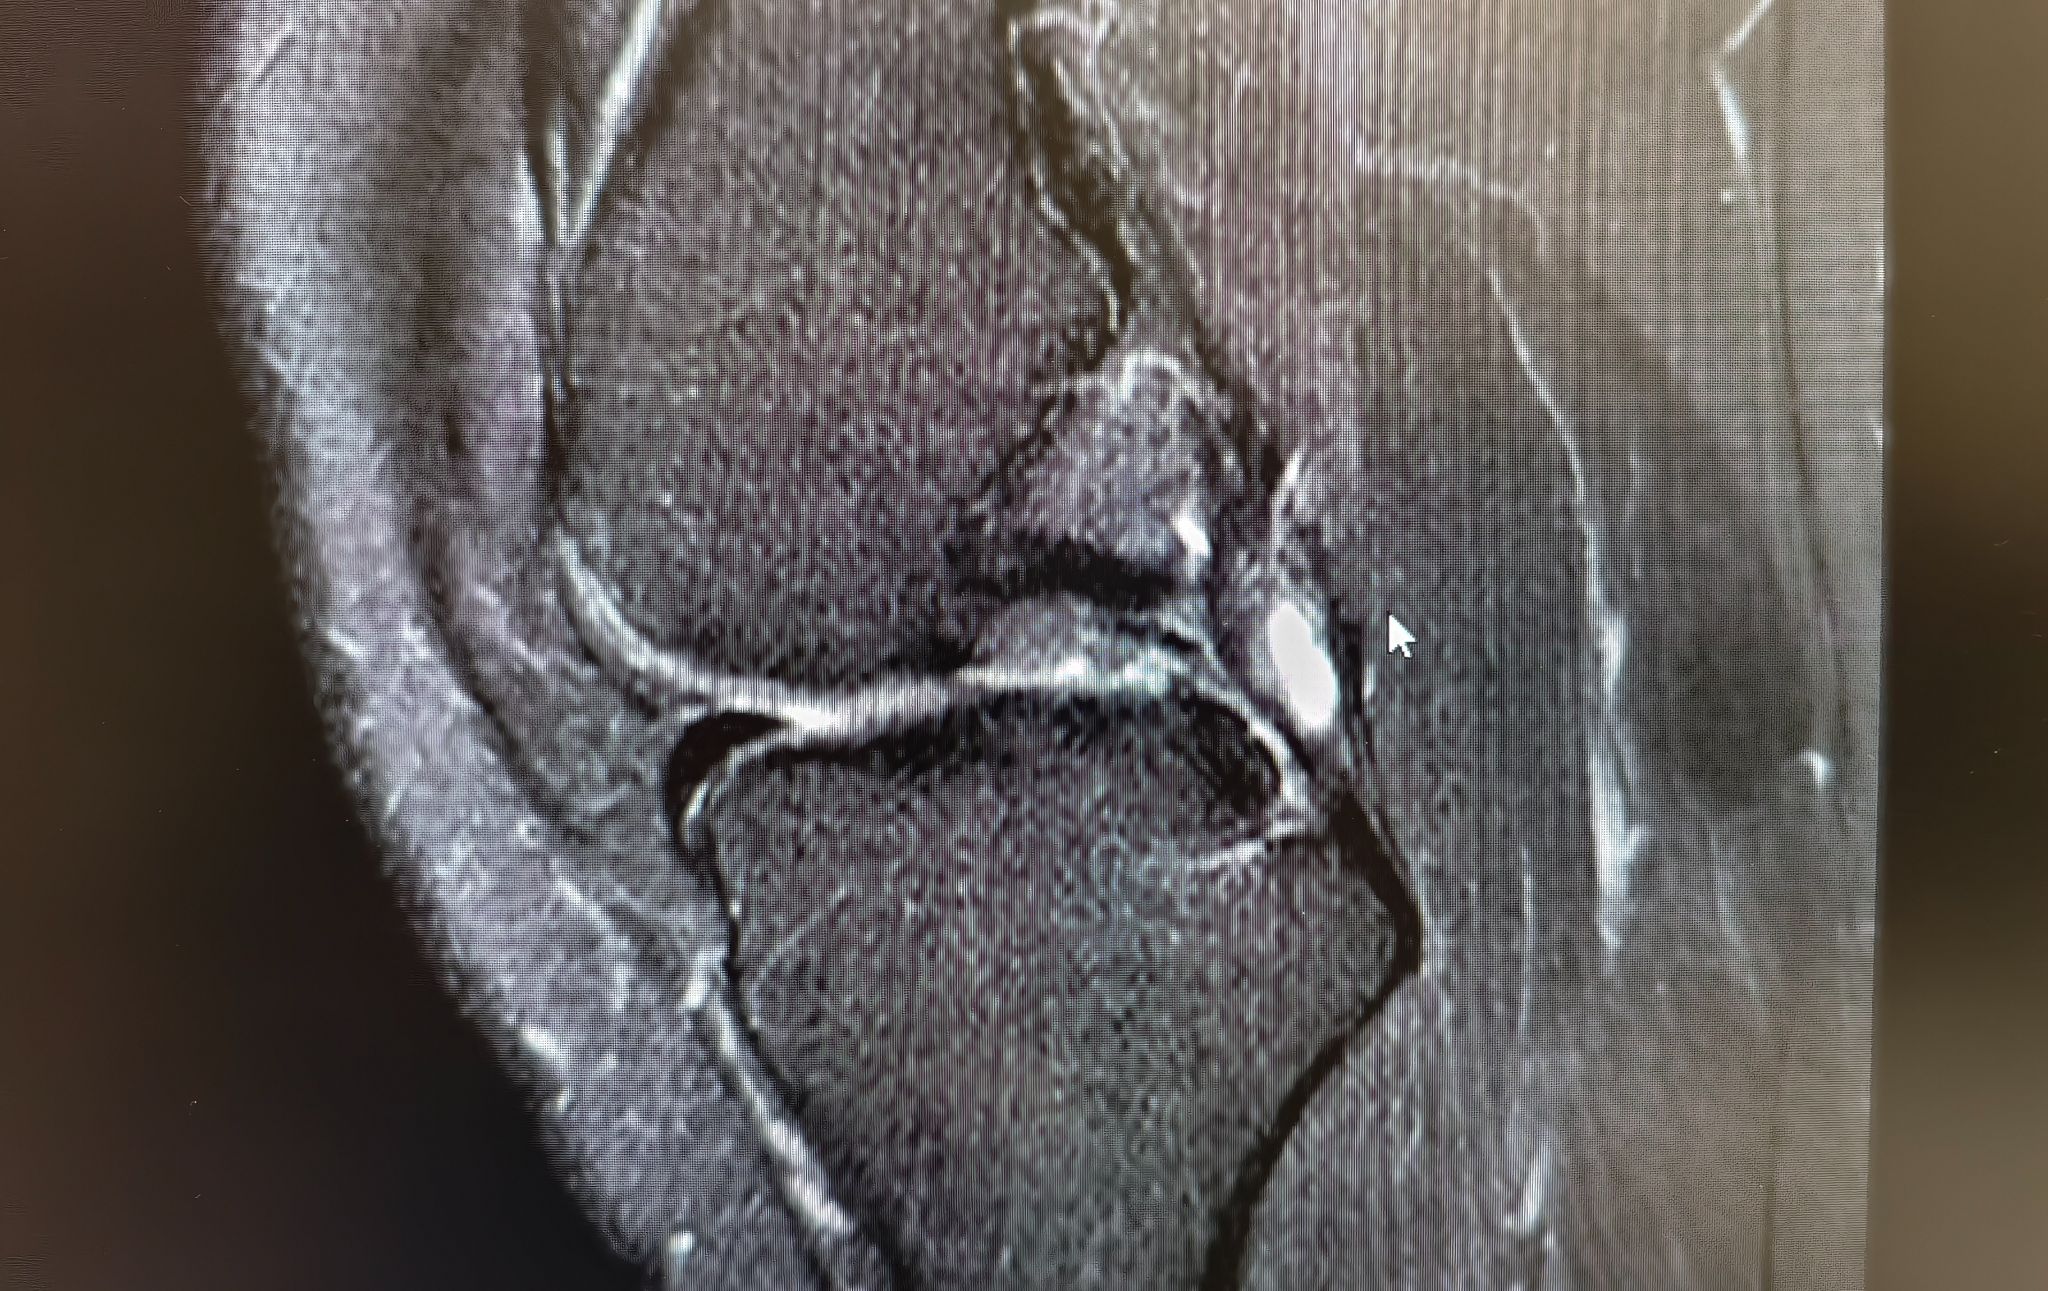

ภาพ mri ประกอบครับ

1. จากภาพประเมินได้เป็นเกรดอะไรบ้างครับ

แพทย์ 2-3 ท่านบอกว่า น่าจะอยู่ที่ระดับ 2 ค่อนไป 3